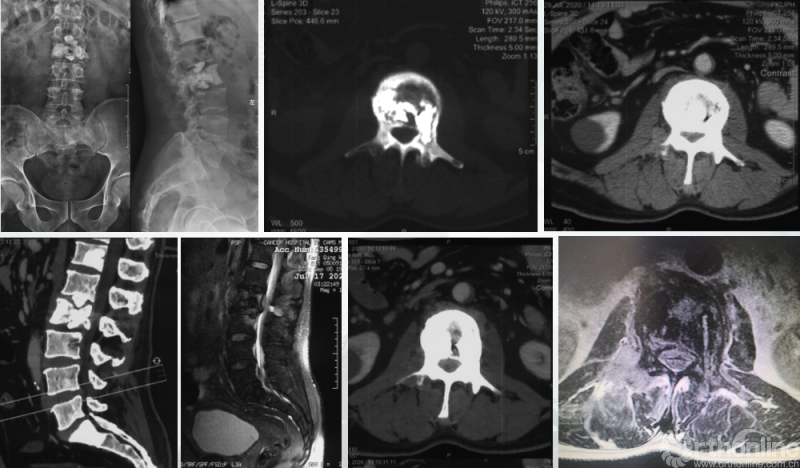

影像学资料

PVP治疗

术后6个月

患者腰椎转移瘤术后9个月,因“腰痛伴右下肢疼痛麻木2个月”再次入院。既往在PVP术后曾行化疗及服用埃克替尼靶向药物维持治疗,查体一般状况良好,自主行走,右大腿前外侧麻木。

入院影像学资料

经脊柱转移瘤专业评估,ESCC分级为Grade2,对放疗不敏感;SINS评分8分,中度不稳。Karnofsky功能状态评分90%,预计生存时间6个月。NOMS流程建议分离手术和SRS。

患者房某,男性、51岁。主因“腰痛3个月”入院,既往外院诊断“周围型肺腺癌”,全身检查提示多发骨转移。

经Spine Oncology Study Group(SOSG)评估硬膜外脊髓压迫(ESCC)为Grade 1a型,轻度脊髓压迫;脊柱机械稳定性评估(SINS)7分,中度不稳。修正Tokuhashi评分(RTS)6分,预计生存<6个月,建议姑息性手术及保守治疗;结合Tomita评分系统6分,故行姑息性手术短期控制。